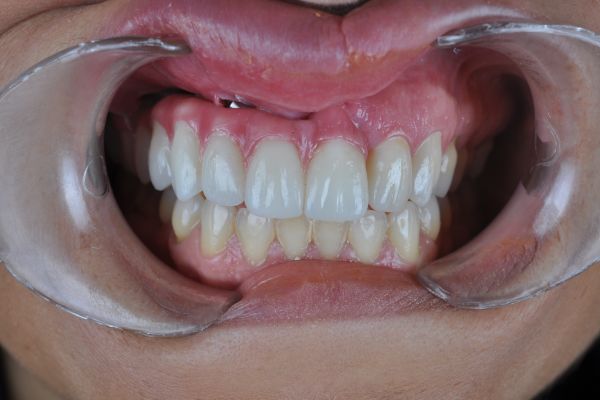

El reto del abordaje quirúrgico en la rehabilitación sobre un implante unitario en un caso de alto requerimiento estético del sector anterior. Descripción a propósito de un caso

Manejo de un defecto estético en maxilar anterior con injertos de tejidos duros y blandos e inserción diferida de un implante dental. A propósito de un caso

The challenge of the surgical approach in the rehabilitation of an anterior sector unitary implant in a case of high aesthetic requirements; case report

Resolución de un caso con implicación estética en el sector antero-superior. A propósito de un caso

Manejo quirúrgico y restaurador de un implante en área estética y evaluación volumétrica tras un injerto de tejido conectivo desepitelizado. Descripción de un caso clínico